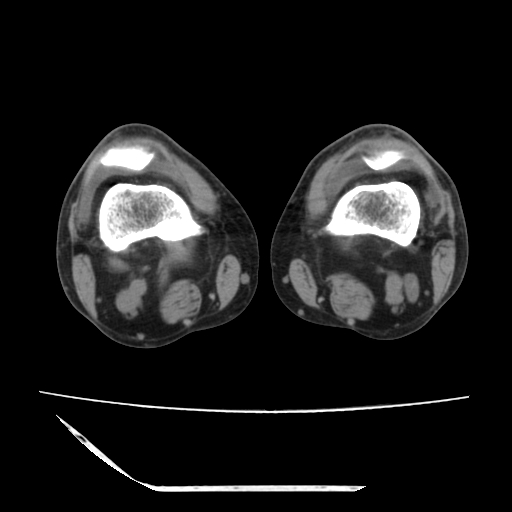

标题: CT13225:老年男性,左膝关节疼痛数月;请各位老师讨论。 [打印本页]

标题: CT13225:老年男性,左膝关节疼痛数月;请各位老师讨论。

骨质增生,骨性关节面硬化,关节积液,考虑退行性骨关节病

关节腔内少量积液,关节面退变。

双膝退变

骨质增生,骨性关节面硬化,关节间隙失常,关节积液,考虑退行性骨关节病.

骨质增生,骨性关节面硬化,关节积液,考虑退行性骨关节病。

这个病例诊断:退行性骨关节炎